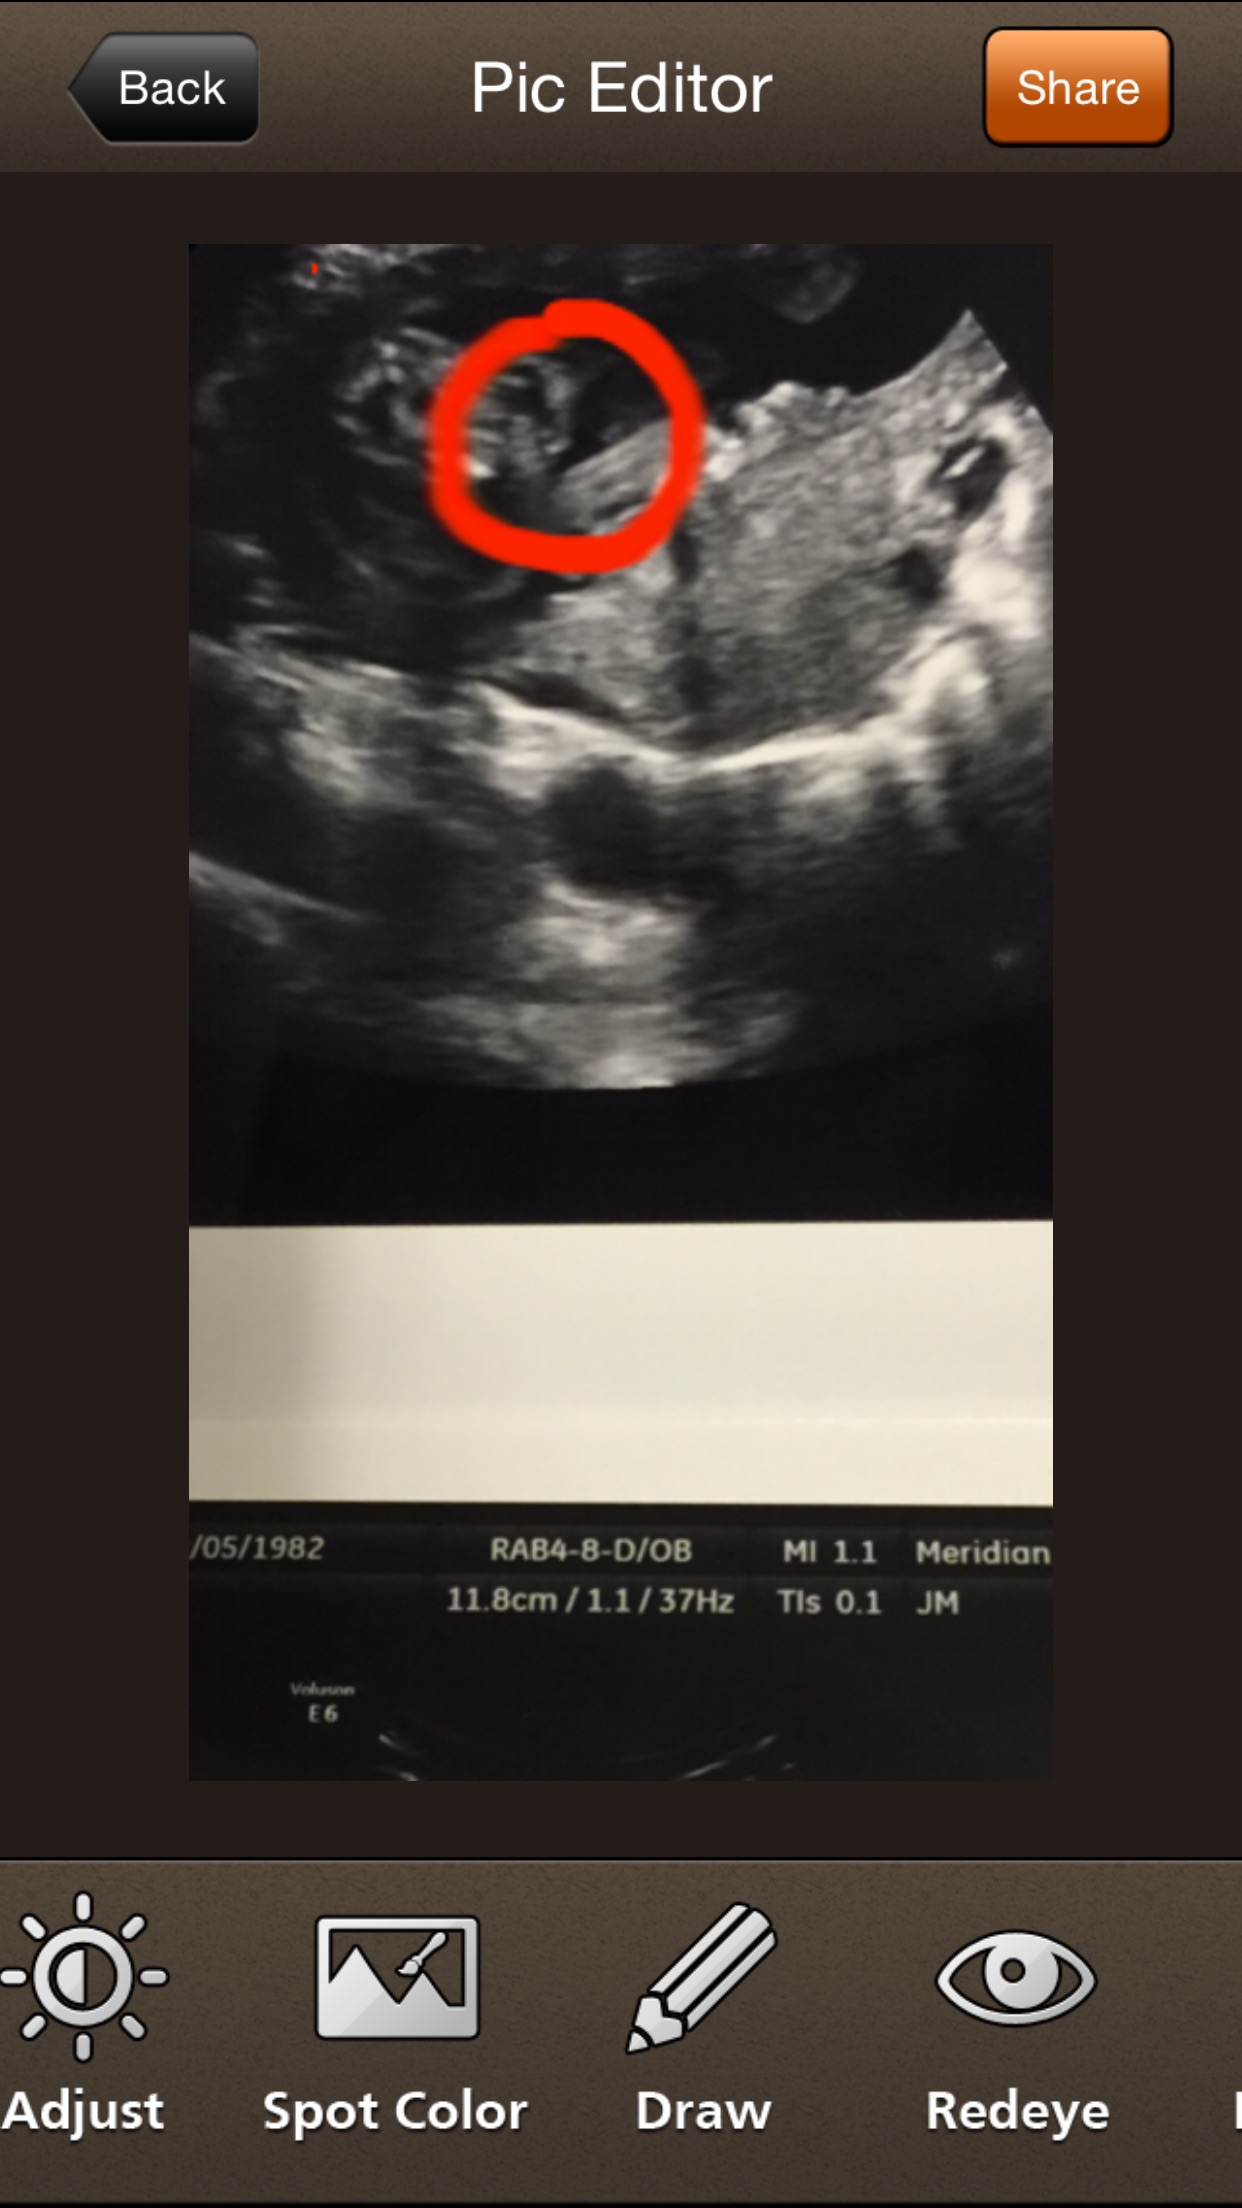

Well I had a doc appt today and tech was there and asked her what I was looking at. She said this is babies GIRLS back side sitting in her leg. I totally thought I was having a boy so a bit upset but am

Just happy baby is healthy. I am shocked maybe by some chance she is wrong...Attachment 29927Attachment 29928